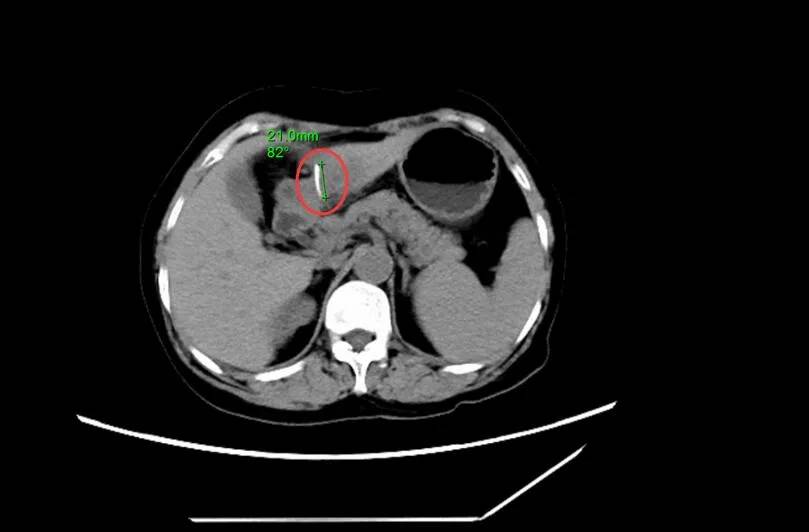

▲影像图片中鱼刺清晰可见。

据医生介绍,在手术中看到,鱼刺连通胃壁和肝左外叶,取出的鱼刺长2.1厘米。手术用时约两个小时,过程比较顺利。手术后,该女子经过7天的治疗观察后顺利出院。